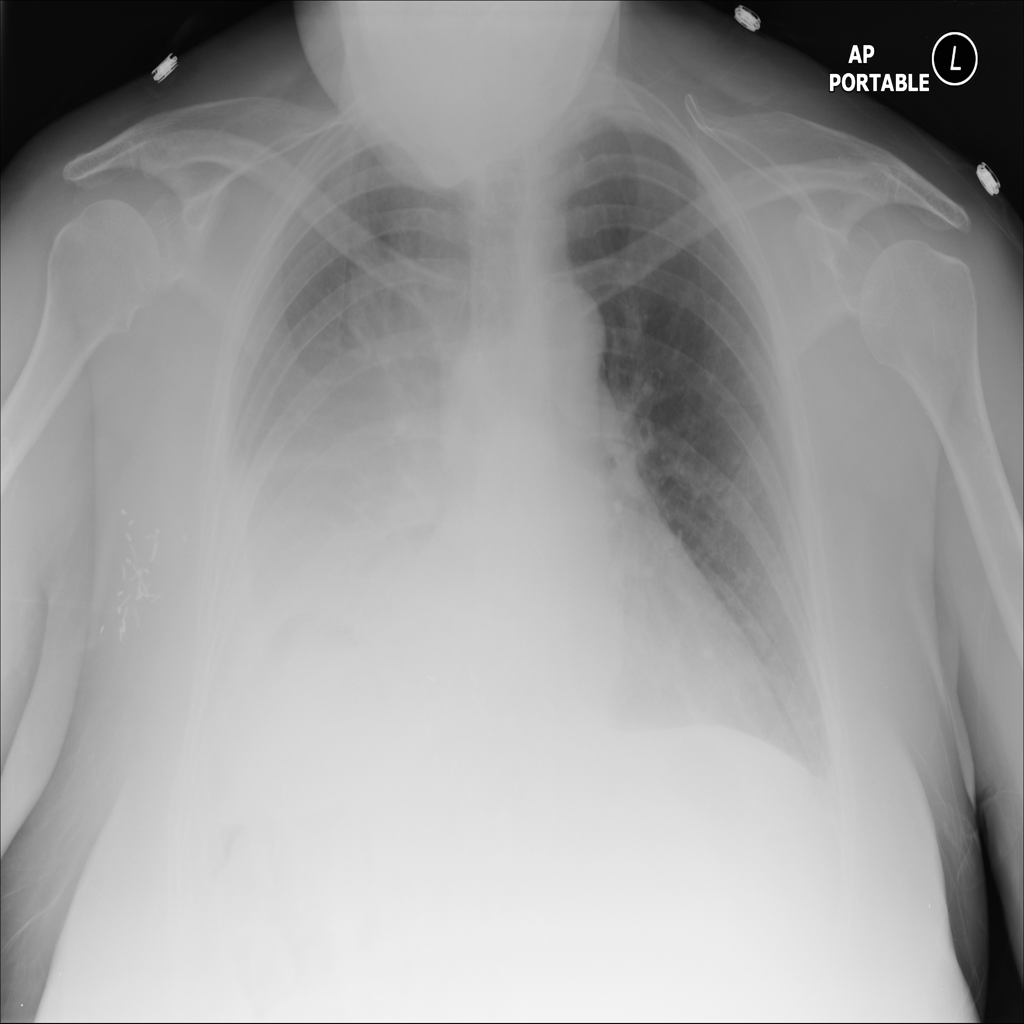

PAT-E81B · IMG-000Effusion

PAT-E81B · IMG-000

PA